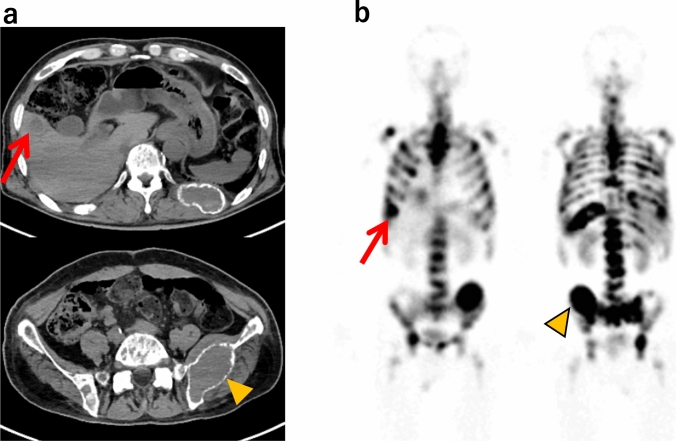

Results: The clinical data of 24 patients with metastatic neuroendocrine tumors (NETs) were analyzed, of whom 16 patients completed the standard protocol 177Lu-DOTATATE treatment. The most common adverse events were hematologic toxicities. Eight patients did not complete the standard protocol treatment, primarily due to adverse events (6/8). Single variable logistic regression analysis revealed that the presence of somatostatin receptor scintigraphy (SRS) positive bone metastases (OR = 21.0, 95% CI 2.37-186, p = 0.006) and lower hemoglobin levels (OR = 0.479, 95% CI 0.255-0.900, p = 0.022) were significantly associated with incomplete treatment. Notably, 5/8 patients in the incomplete group had extensive bone metastases (> 20 lesions), including 4 with diffuse metastases. Other variables, including age, sex, white blood cell count, platelet count, eGFR, and other metastatic sites, showed no significant association with treatment completion.

Conclusions: In this study, the presence of SRS-positive bone metastases and low hemoglobin levels were significant factors associated with the inability to complete 177Lu-DOTATATE treatment for NET patients. Extensive bone metastases, such as diffuse metastasis or more than 20 bone metastases, may be particularly associated with the inability to administer standard protocol treatment.